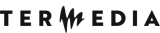

Whole-body MRI enables the investigation of systemic spread of malignant neoplasms and is cautiously recommended in their diagnostics and staging in children as well as in the surveillance in cancer predisposition syndromes [36]. In our centre WB-MRI is used routinely in children with ES, RMS, neuroblastoma, and Langerhans cell histiocytosis. The diagnostic and staging scheme for suspected malignant bone or soft tissue tumours is shown in Figure 11.